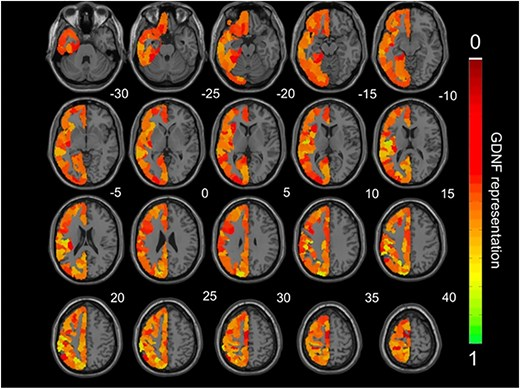

🚨New study alert in @Psychoradiology!🧠 How do peripheral GDNF levels influence the depressed brain? This study by Fennan Jia et al. reveals the relationships between glial cell line-derived neurotrophic factor, brain circuits, and clinical symptoms in depression.#MDD #fMRI #DMN

x.com/PSYRAD2/status… Results: A new study reveals a novel mediation pathway in the depressed brain: 📉✨ 🔹Serum: MDD patients showed significantly reduced GDNF and IL-8 levels. 🔹DMN: Interaction effects in fALFF within both DMPFC and MTL subsystems.#Depression #fMRI #DMN

Psychoradiology tweet mediaPsychoradiology tweet media

x.com/PSYRAD2/status… Final Takeaway:🧠🧩 ✅Establishing a novel molecular–neural pathway where DMN activity mediates the link between GDNF and rumination in MDD. ✅Highlights GDNF as a potential therapeutic target for depression. Follow #Psychoradiology for more!🔔#Depression

x.com/PSYRAD2/status… Methods🔬📊: 🔹Sample: 33 MDD patients vs 33 HC. 🔹Task: fMRI during a sustained, active rumination task & RRS assessment. 🔹Imaging: fALFF and functional connectivity within DMN subsystems. 🔹Biomarkers: Quantified serum GDNF and inflammatory markers.#MDD